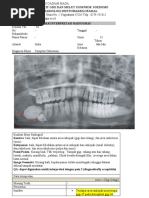

D. Maryland Bridge pada gambar di atas?

D. Restorasi cepat aus

E. Prosedur laboratorium lebih simple daripada metode

soft machining

8. Jahitan yang paling sering digunakan dalam bidang A. kelas I C mesioangular

kedokteran gigi adalah B. kelas I A mesioangular

C. kelas I A horizontal

A. Jahitan simpul tunggal

D. kelas II A horizontal

B. Jahitan matras Horizontal

E. kelas II A mesioangular

C. Jahitan Matras Vertikal

D. Jahitan simple continuous

E. Jahitan figure of eight 12. Pada pemeriksaan radiografis didapatkan deskripsi

gambaran ruangan yang tersedia antara bagian distal gigi

molar dua dengan ramus mandibula hanya cukup

9. Pasien perempuan datang dengan keluhan nyeri pada

sebagian untuk ukuran mesio-distal mahkota gigi molar

rahang bawah sebelah kiri. Pasien telah melakukan foto

tiga yang impaksi, dan puncak tertinggi molar ketiga

panoramik. Apakah diagnosis dari gambar di bawah ini

berada dibawah servikal molar kedua. Apakah Klassifikasi

menurut klasifikasi impaksi pell and gregory?

pell and gregory yang paling tepat…

A. IIIB

B. IIC

C. IC

D. IIB

E. IIIC